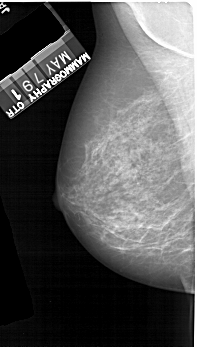

A_1894_1.LEFT_MLO

LEFT_MLO LINES 5191 PIXELS_PER_LINE 2941 BITS_PER_PIXEL 12 RESOLUTION 43.5 NON_OVERLAY